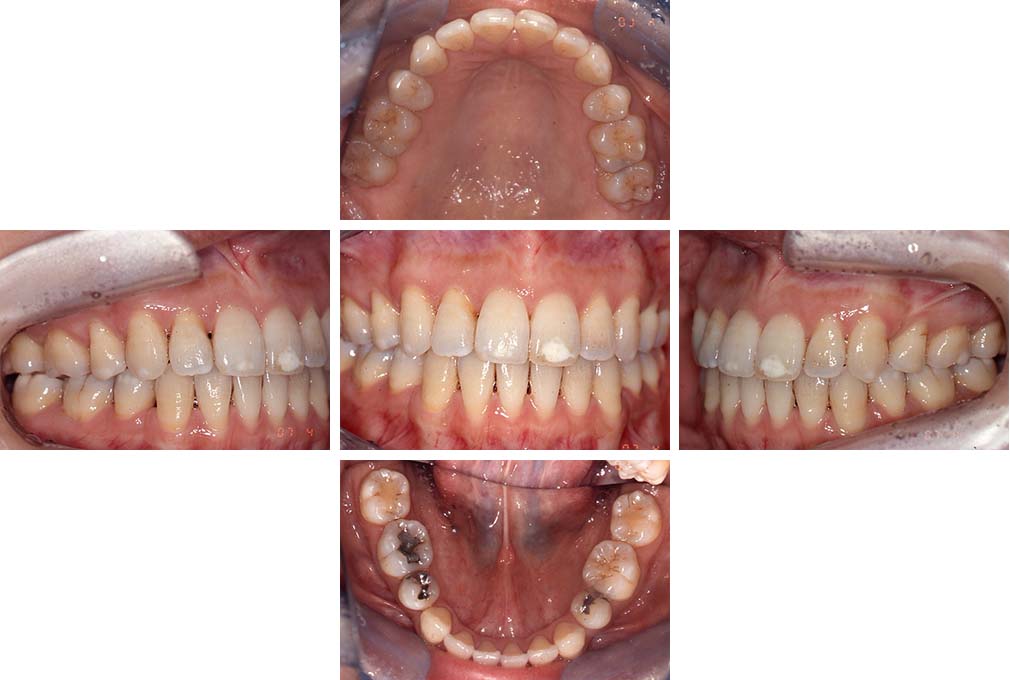

CASE:02

下顎前歯部叢生、小臼歯4歯先天欠損

初診時年齢 14歳3か月

性別 女性

治療費の目安 70万円(治療開始時)

上顎左右側小臼歯3歯、下顎左側第二小臼歯の先天欠損と下顎前歯の叢生を主訴として近隣一般歯科から紹介来院した。

上顎左側第一、第二小臼歯、右側第一小臼歯、下顎左側第二小臼歯が先天欠損であったが、左上第二乳臼歯の根の吸収がほぼ無いことから、これを残すこととして、下顎左側乳臼歯と、右側第二小臼歯を抜歯していただきマルチブラケット装置を使用して動的治療を行った。矯正用ゴムなどの協力状態も良く2年0カ月(調整来院19回)で装置を撤去し保定へ移行した。動的治療終了13年2カ月での来院時には下顎左右側智歯が萌出していたが、垂直的に萌出していたため抜歯は行っていない。

治療前

14歳3か月

治療後

動的治療期間2年0カ月

16歳7か月

13年経過

動的治療終了後13年2カ月

30歳0か月